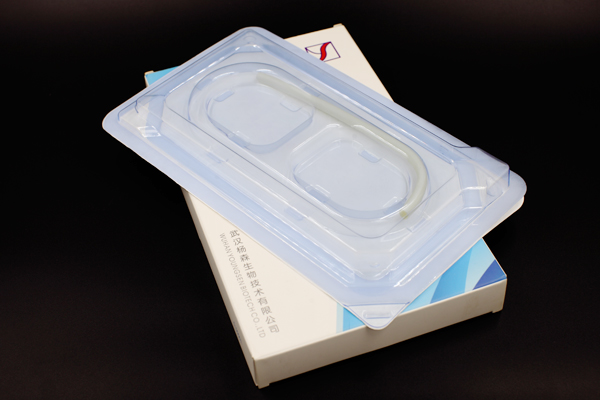

jinnian金年会成立于2009年4月,是集团旗下专业从事高端医疗器械研发、生产与销售的国家高新技术企业,坐落于国家级生物产业基地-武汉光谷生物城。现拥有1000m²符合GMP要求的万级洁净厂房;授权和受理国内外发明专利近20项;2017、2018年连续两年承担国家重点研发计划项目。